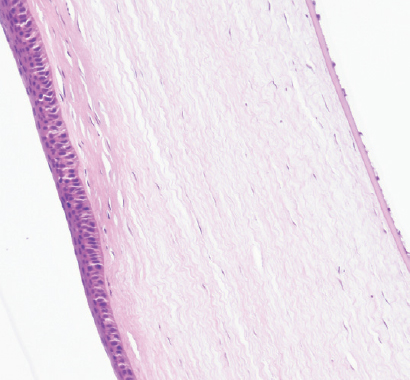

Режим 6. При данной мощности в месте воздействия роговица имеет нехарактерный вид. Эпителий полностью покрывает место вмешательства, однако базальные клетки эпителия кубические, сам эпителий истончён, неплотно прикреплён к строме. Строма в области повреждения практически на 1/4–1/3 толщины образована неплотно лежащими коллагеновыми волокнами с большим числом фиброцитов и единичными лимфоцитами. Десцеметова мембрана и энодотелий без изменений (рис. 4).

Рис. 4. Фрагмент роговицы через 3 мес. после воздействия в подгруппе 1а. Фульгурация, режим 6. Окраска гематоксилином и эозином. Увеличение ×40

Fig. 4. Fragment of the cornea 3 months after exposure in subgroup 1a. Fulguration, mode 6. Stained with hematoxylin and eosin. Magnification ×40

На первом этапе эксперимента воздействие на роговицу в режиме 5 как клинически, так и гистологически выглядело недостаточным. Изменения охватывали лишь 10–15 % передней стромы. Учитывая, что в норме толщина роговицы кролика в центре составляет примерно 350 мкм, воздействию подвергались лишь около 50 мкм стромы. При воздействии в режиме 6 и 7 через 3 мес. изменения стромальной структуры распространялись примерно на 150 мкм. Воздействие в режиме 8, по нашему мнению, является избыточным. У кролика на этом режиме воздействия были самые грубые изменения в строме. Кроме того, в патологический процесс вовлекалась десцеметова мембрана.